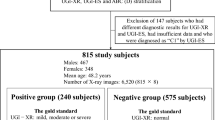

This work aimed to improve the early clinical diagnosis rate of atrophic gastritis (AG) and reduce the risk of disease deterioration or cancerization. Three hundred and eight patients with gastric disease were taken as the research object, who were divided into two groups: AG (n = 159) and non-AG (n = 149), according to the diagnosis results. The gastric antrum images of patients were collected, and the DenseNet model for gastric antrum image lesion screening was improved. Then, the differences in serum pepsinogen (PG I and PG II) of patients were detected, and the efficiency of different methods to screen AG was compared. The results revealed that the levels of PG I and PG II in AG patients were substantially reduced, and the sensitivity (70.44%), specificity (66.44%), and accuracy (68.51%) of AG diagnosis by indicator PG I were higher than that of PG II and joint diagnosis. The diagnosis accuracy rate of AG based on the improved DenseNet model was 98.63%. The accuracy of model recognition combined with serological indicators for disease diagnosis was as high as 99.25%, with a sensitivity of 96.17% and a specificity of 94.33%. In summary, the combination of deep learning-based image recognition methods and serological specific indicators could improve the clinical diagnosis rate of AG, which could provide a reference for the subsequent clinical adoption of artificial intelligence recognition technology.